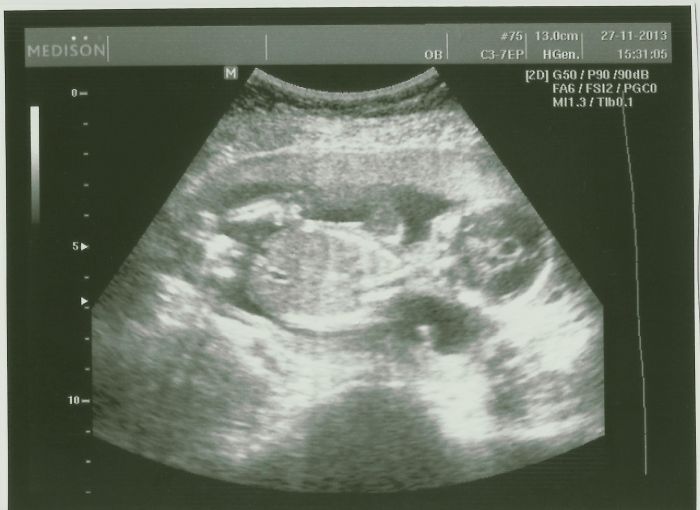

Tak jsem dnes byla na domluveném utz s manželem :) Budoucímu taťkovi se to moooc líbilo :) Malej se drbal na hlavě a pak se začal neuvěřitelně kroutit :D Bylo to bezva a oba jsme si to užili :) Díky Bohu za tak skvělou doktorku

[396264] Eviku, to jsou kouzelny obrazky! :-)) Ty rucicky a nozky, nadhera!

[396267] Děkuju Evi :) Malej se dneska opravdu snažil